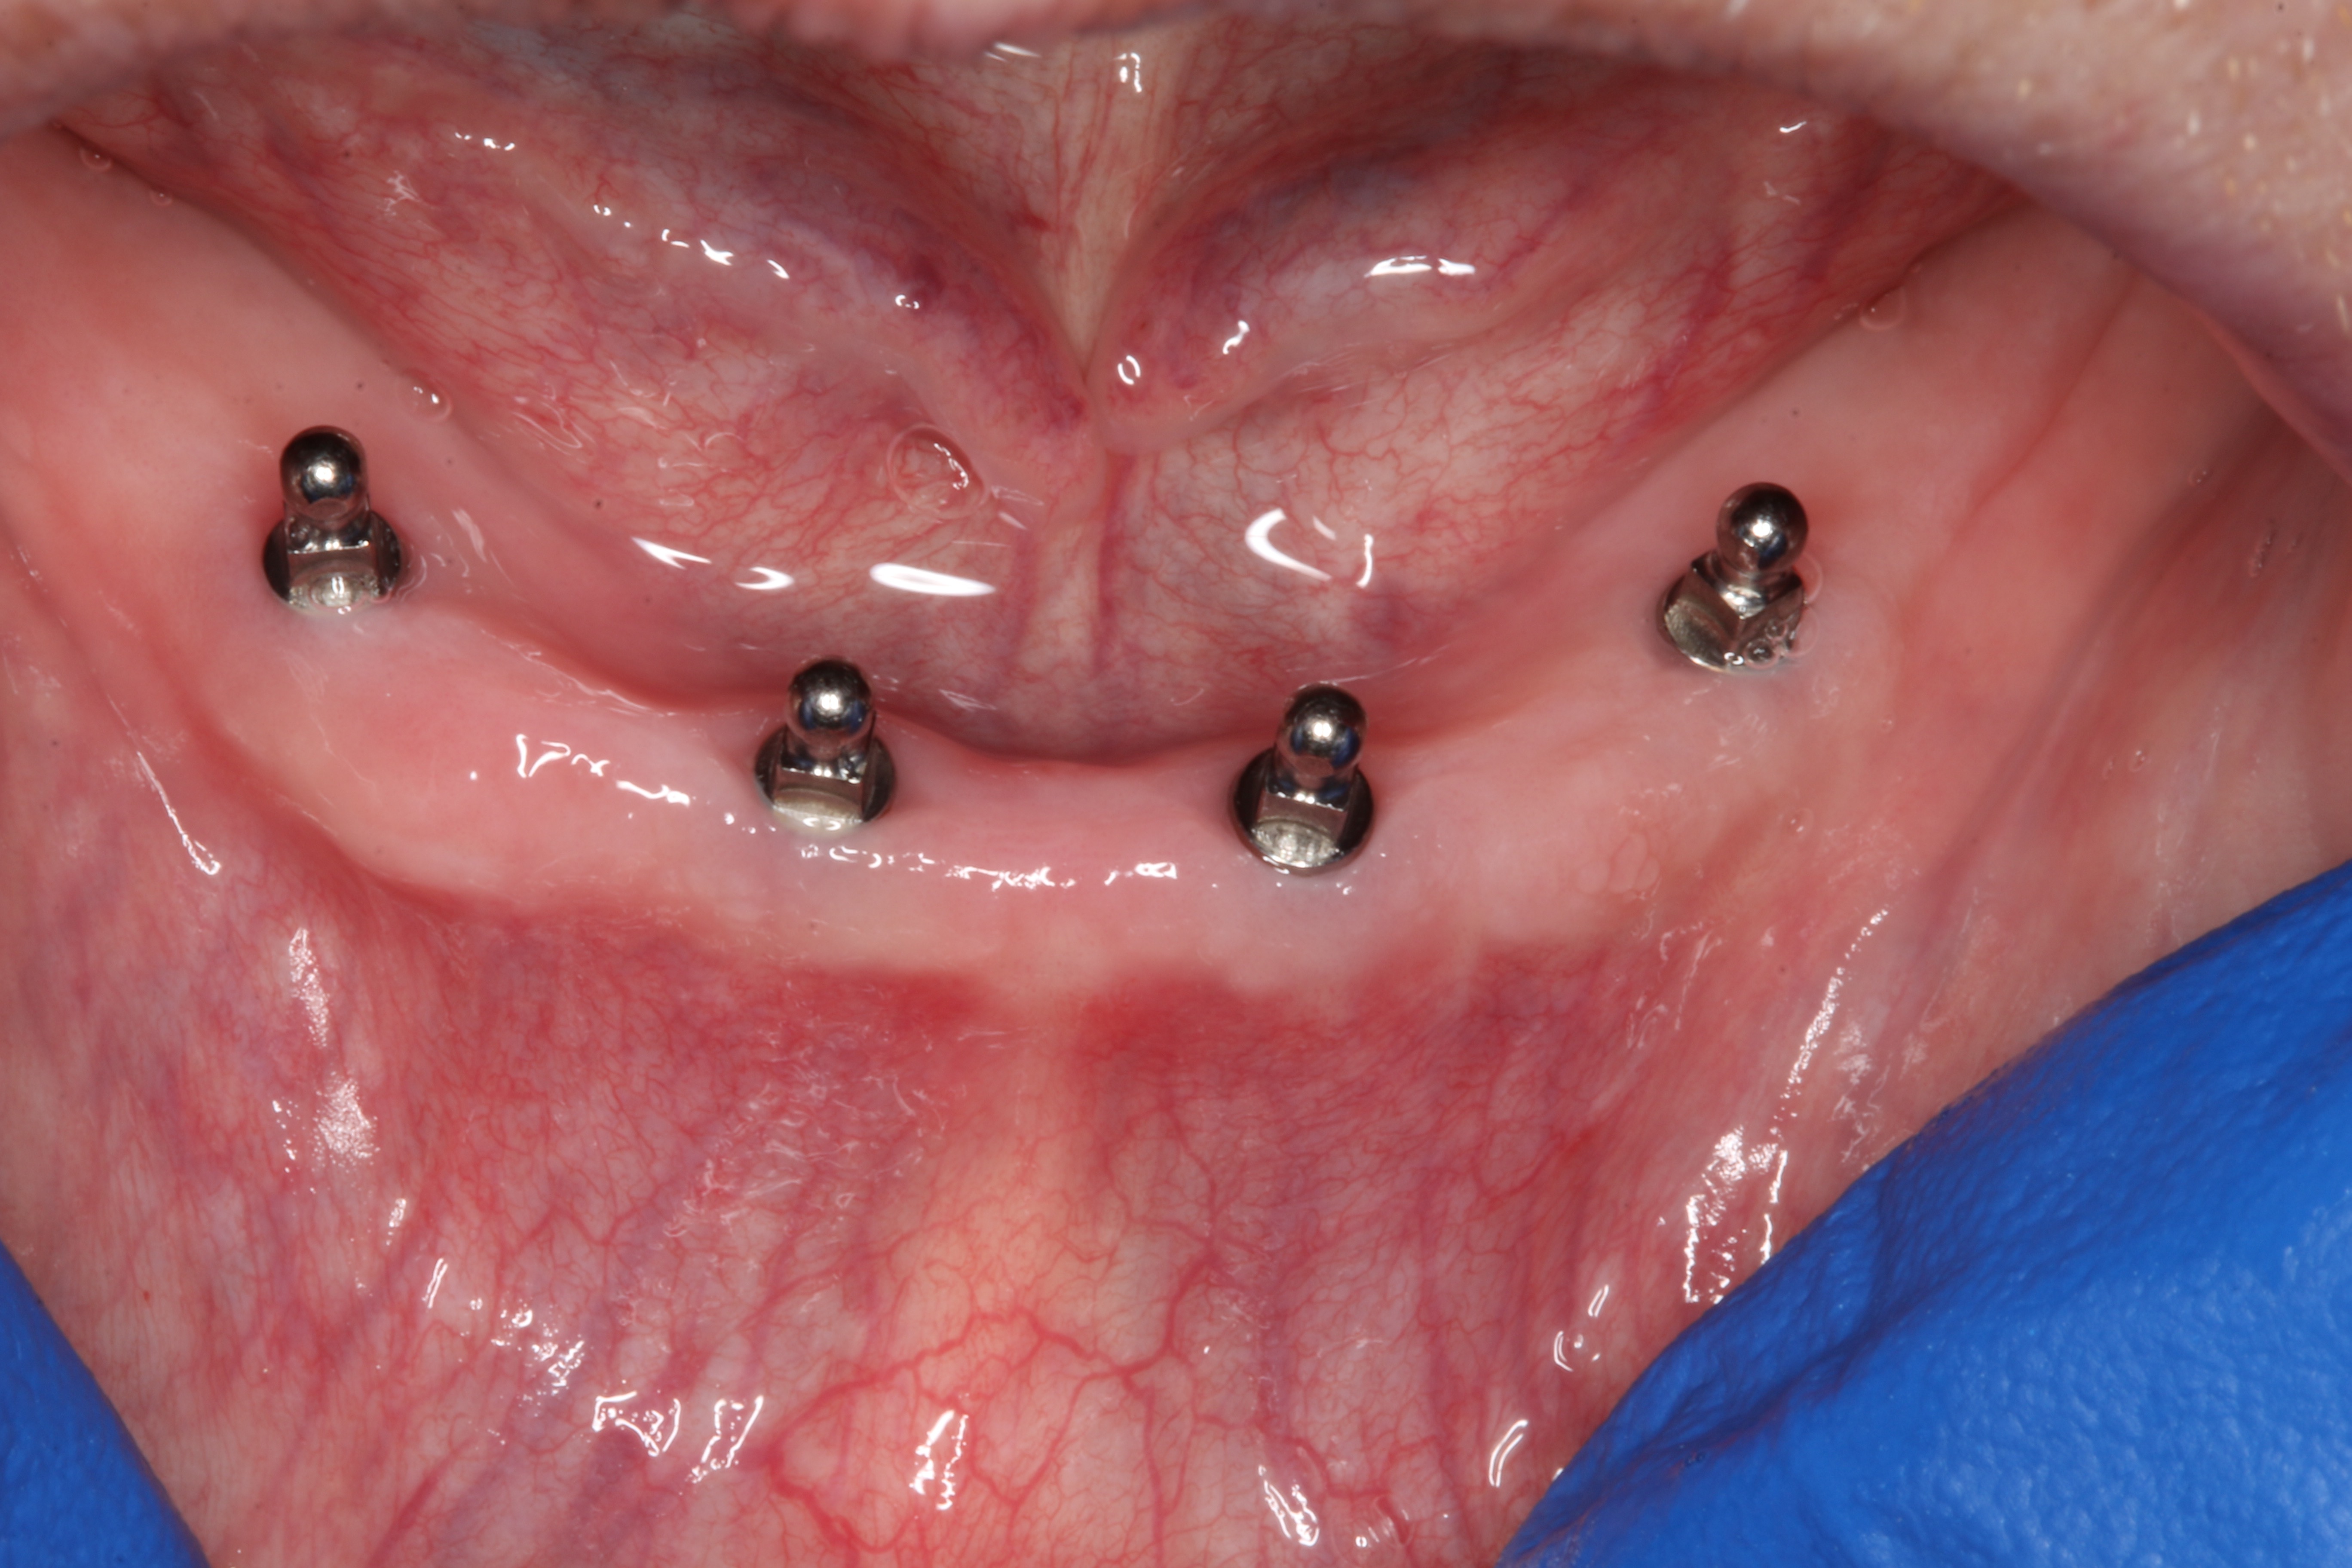

In a statement of position, the American Academy of Oral and Maxillofacial Radiology recommends that a form of cross-sectional imaging be used to guide surgical implant placement.20 In this case a small-volume cone-beam computed tomography (CBCT) scan was taken of the anterior mandible to further develop the surgical plan. From these images the position of the mental foramen and any anterior loop of the mental nerve was established (Figure 1). Given the length and width of bone, four 2.4-mm-wide by 13-mm-long implants were chosen for this case. The position of the two distal implants would allow for a margin of safety in regards to the mental nerve but would be placed as far posterior to the two most anterior implants as allowable. Maximizing the anterior-posterior, or A-P, spread of the implants would minimize any cantilevering forces acting on the denture.

Fig 1. CBCT image of the mandible with implants superimposed

Figure 1